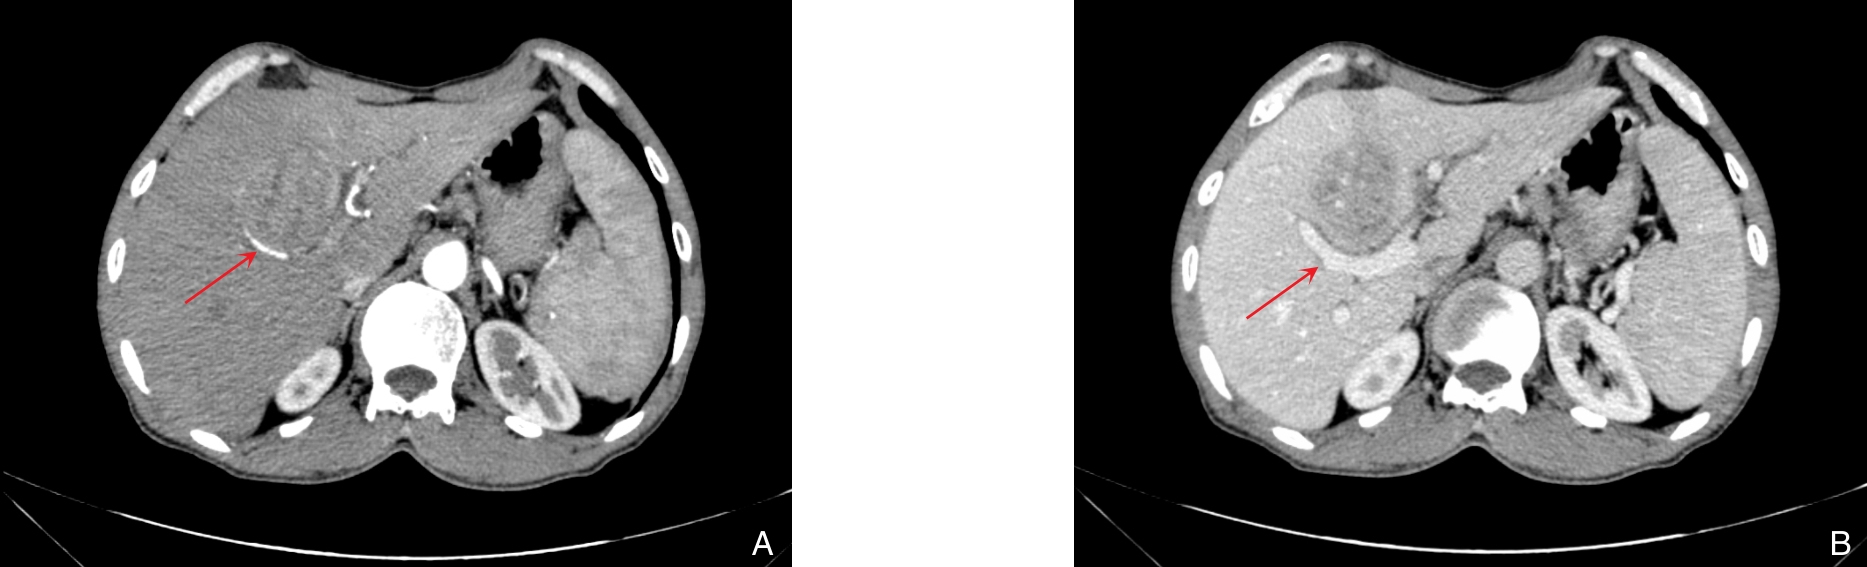

摘要:背景与目的 恶性黑色素瘤常见于皮肤及眼部等部位,肝脏原发极为罕见,且缺乏特异性临床与影像学特征,易被误诊。本文报告1例肝脏原发性黑色素瘤(PHM),并结合文献回顾分析其临床特点、诊疗策略及预后。方法 回顾性分析1例经手术切除并病理确诊的PHM患者,检索中国知网、万方、维普及PubMed数据库相关病例,共纳入42例进行总结。结果 患者,男性,61岁,术前误诊为肝细胞癌,术后免疫组化示HMB45、Melan A、SOX10强阳性,确诊为PHM。行手术完全切除肿瘤,术后12个月复发并多发转移。文献分析显示,PHM多见于中老年男性,临床表现不典型,影像学缺乏特异性,确诊依赖病理及免疫组化。预后较差,25例有随访资料的患者中,6个月和12个月生存率分别为28.00%和12.00%。结论 PHM是一种罕见且预后不良的恶性肿瘤,早期诊断困难。手术切除仍是局限性病灶的首选治疗,结合分子靶向及免疫治疗可望改善生存;失去手术机会时,应优先考虑免疫治疗和靶向治疗的个体化方案。